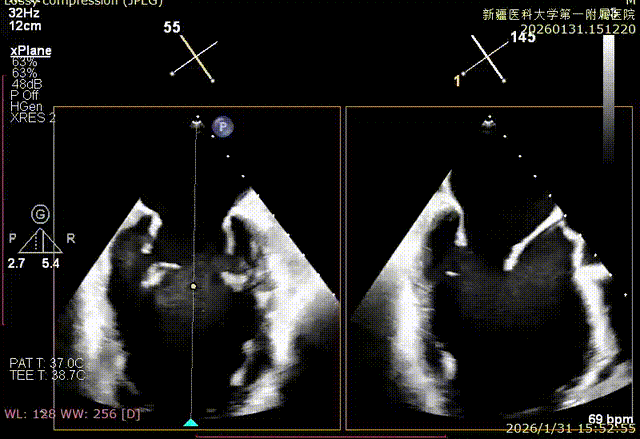

XPLAN切面2区后叶栓系

XPLAN切面中重度反流

XPLAN后叶严重栓系

Bicom切面中重度反流